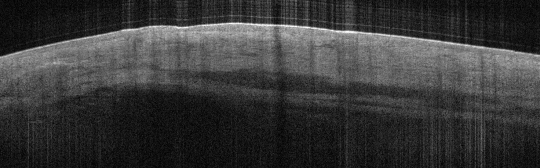

VA15: Right Dorsal Hand, Squamous Cell Carcinoma, Invasive, Keratoacanthoma type

- Arrows indicate extent of squamous mass

VA15: Right Dorsal Hand, Adjacent, Normal